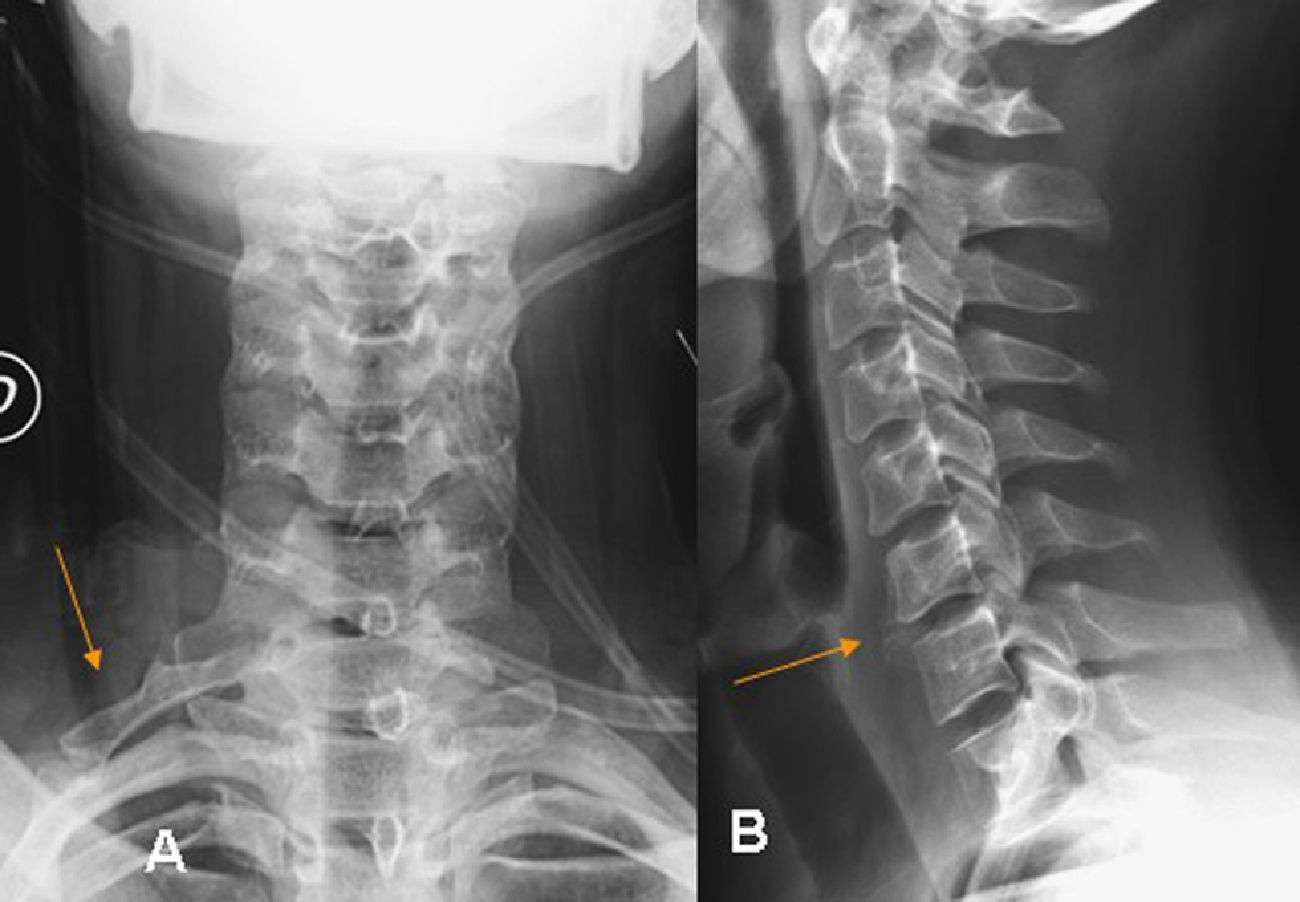

El objetivo de este trabajo es realizar una revisión general de las manifestaciones en la radiografía simple del amplio espectro de patologías que pueden ser responsables del dolor generado en la columna vertebral. Este espectro abarca la patología congénita, traumática, degenerativa, tumoral, inflamatoria e infecciosa.

The aim of this article is to review the manifestations on plain-film radiography of a wide variety of diseases that can cause back pain, including congenital, traumatic, degenerative, tumor-related, inflammatory, and infectious diseases and processes.